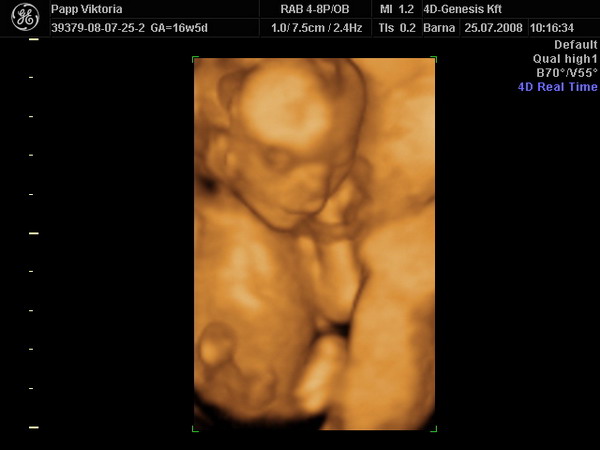

sziasztok! Szuper volt a 4D és KISFIÚ :lol: :lol: :lol: :lol: :lol:

Kép kis csomag:)

Kép pofi, pocak és kukac:)

Kép

De jó képek! És gratula a kisfiúhoz.

a második képen milyen édesen tartja a lábait. És a harmadik is nagyon jó. Kire hasonlít? Tiszta Anyja, nem? :lol:

Vicky, gratulaaaa!!! Ezt a kukacot el se lehet nézni annyira egyértelműen látszik :lol: Szuper, hogy tudjátok a nemét. Neve???